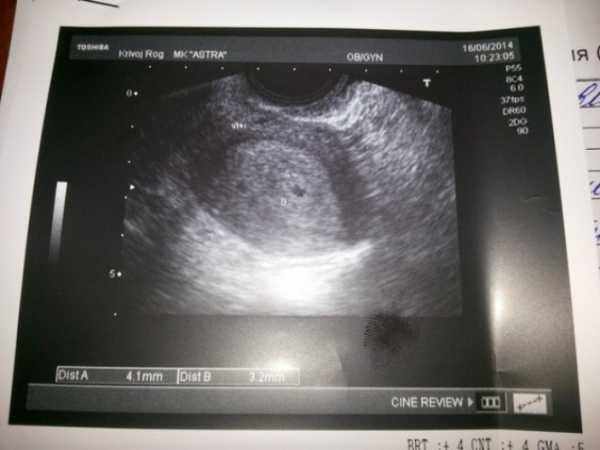

УЗИ

В начале четвёртой акушерской недели исследование вряд чем-то поможет. Зато в конце на качественном оборудовании хороший специалист уже кое-что разглядит. Это будет матка с толстым слоем эндометрия и эмбрион – маленькая чёрная точка. Если у женщины ранее была внематочная беременность, врач-специалист обязательно проверит всю женскую систему.

Фото плода, УЗИ

Эти исследования заключаются, в основном, в назначении врачом анализа на ХГЧ, который подтверждает беременность. Крайне редко делают УЗИ на четвертой неделе беременности, которое может показать желтое тело, определить в матке наличие зародыша. Чаще всего на этом сроке женщины не обращаются к врачу, так как могут и не подозревать о своем положении, а тесты, к сожалению, не всегда ее определяют.

На 4 неделе беременности ультразвуковое исследование может показать только жёлтое тело, которое играет главную роль – обеспечение эмбриона всеми необходимыми питательными веществами до того времени, пока процесс формирования плаценты не закончится. Именно жёлтое тело вырабатывает гормон прогестерон, который отвечает за сохранение беременности. Ультразвуковое исследование на 4 неделе беременности с уверенностью покажет вам, прикрепился ли эмбрион в полости матки или нет. А вот проведение обследования на столь маленьком сроке делается очень редко, ведь на этом этапе женщина только начинает подозревать, что беременна.

Обследование на УЗИ

Ультразвуковое обследование на 4 неделе позволяет обнаружить растущее жёлтое тело, размеры которого могут намекнуть, что имплантация плодного яйца произошла. При использовании высокочувствительного аппарат УЗИ возможно обнаружение самого зародыша. Но проводить такое исследование на столь ранних сроках не рекомендуется, так как это может негативно сказаться на развитии эмбриона.

Сейчас быстро увеличивается головной мозг, и растет голова. Если посмотреть на снимки УЗИ на 4 неделе беременности, то можно разглядеть места зачатков ручек и ножек, лица, ротовой полости.

На фото УЗИ на 4 неделе акушерской беременности будущий малыш выглядит как малюсенькая точка – зернышко мака.

УЗИ на 4 неделе беременности

Если аппарат ультразвукового исследования обладает высокими чувствительными характеристиками, то на 4 неделе беременности на снимках можно рассмотреть не только увеличившееся желтое тело, но и сам зародыш.

Стоит ли проводить УЗИ на столь раннем сроке, решит врач. Хотя вредное воздействие ультразвуковых волн на эмбрион или на саму беременную никак не доказано.